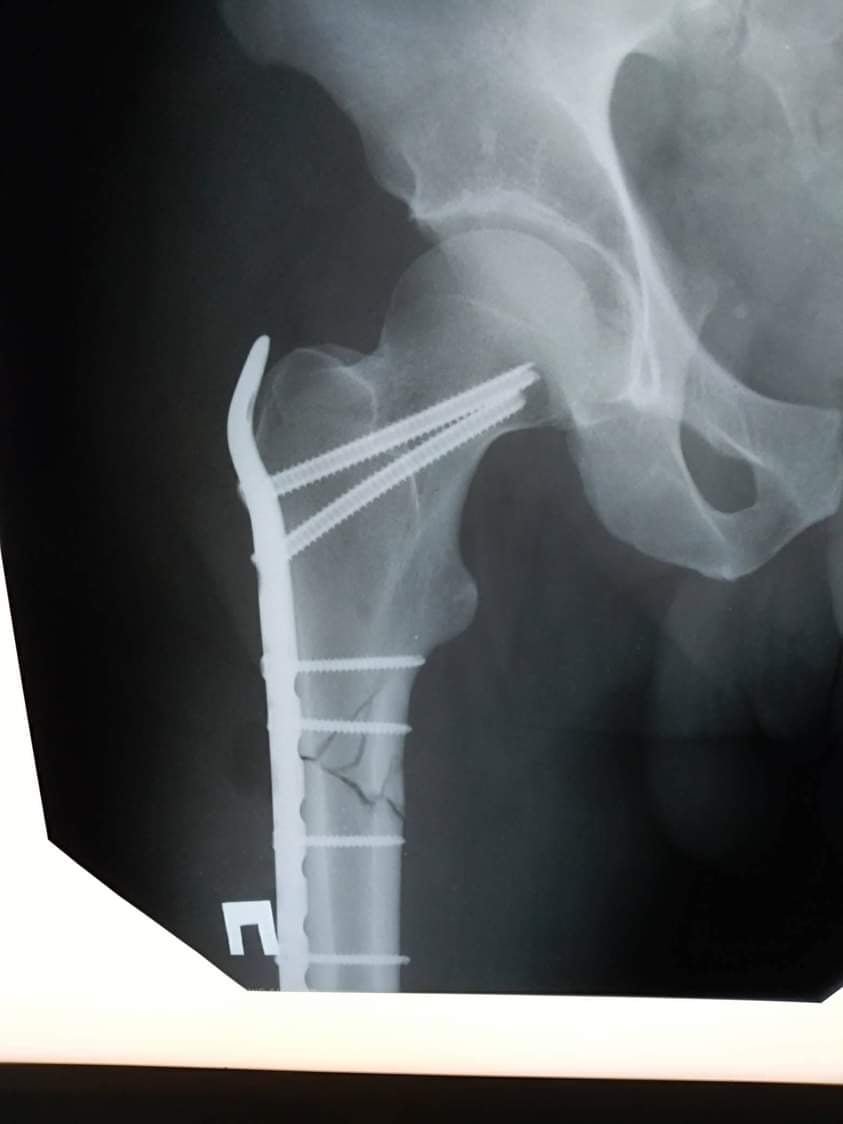

У процесі надання першої медичної допомоги йому встановили діагноз: закритий багатовідламковий перелом верхньої третини правої стегнової кістки із зміщенням уламків. Про це інформують на сторінці закладу у facebook.

Після дообстеження та передопераційної підготовки 18 грудня чоловіку провели операцію - відкриту репозицію МОС (металосинтез) правої стегнової кістки проксинальною LCP пластиною та гвинтами.

Складну операцію, яка тривала протягом трьої годин, успішно проведели лікарі-травматологи: Босий Т.Б., Радчук В.М., та Лотоцький І.А.